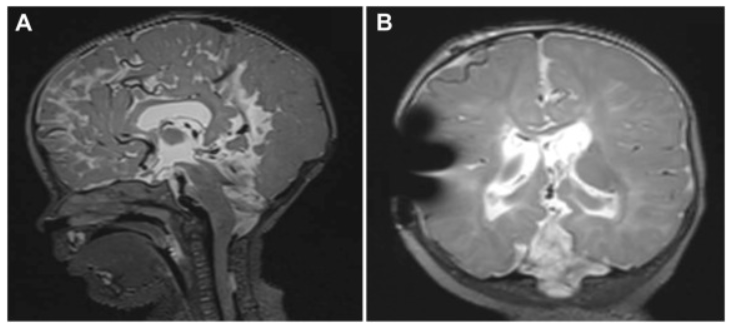

术后患儿一般状态良好,但存在四肢痉挛和眼球震颤。Krauss教授建议应尽早为患儿开始物理治疗,同时需加强语言功能训练并关注心理治疗。然而,鉴于疾病的严重程度,患儿在3岁多时,虽然意识状态无碍,具备基本交流能力,但在运动、语言、智力及认知多个方面均表现出不同程度的发育迟缓和功能缺损。具体表现为:无法独立行走,可自行进食但穿衣动作略显笨拙,虽无明确的神经功能缺陷但运动功能受限,能在家庭环境中与小朋友玩耍,面对陌生人时则表现出警惕性。

随访影像学检查显示,患儿的后脑疝出及颈髓空洞症已消退,巨大的脑膨出完全消失。然而,胼胝体、顶叶及枕叶仍存在多种脑部结构异常,并伴有小脑萎缩。患儿的智力水平明显低于正常儿童。